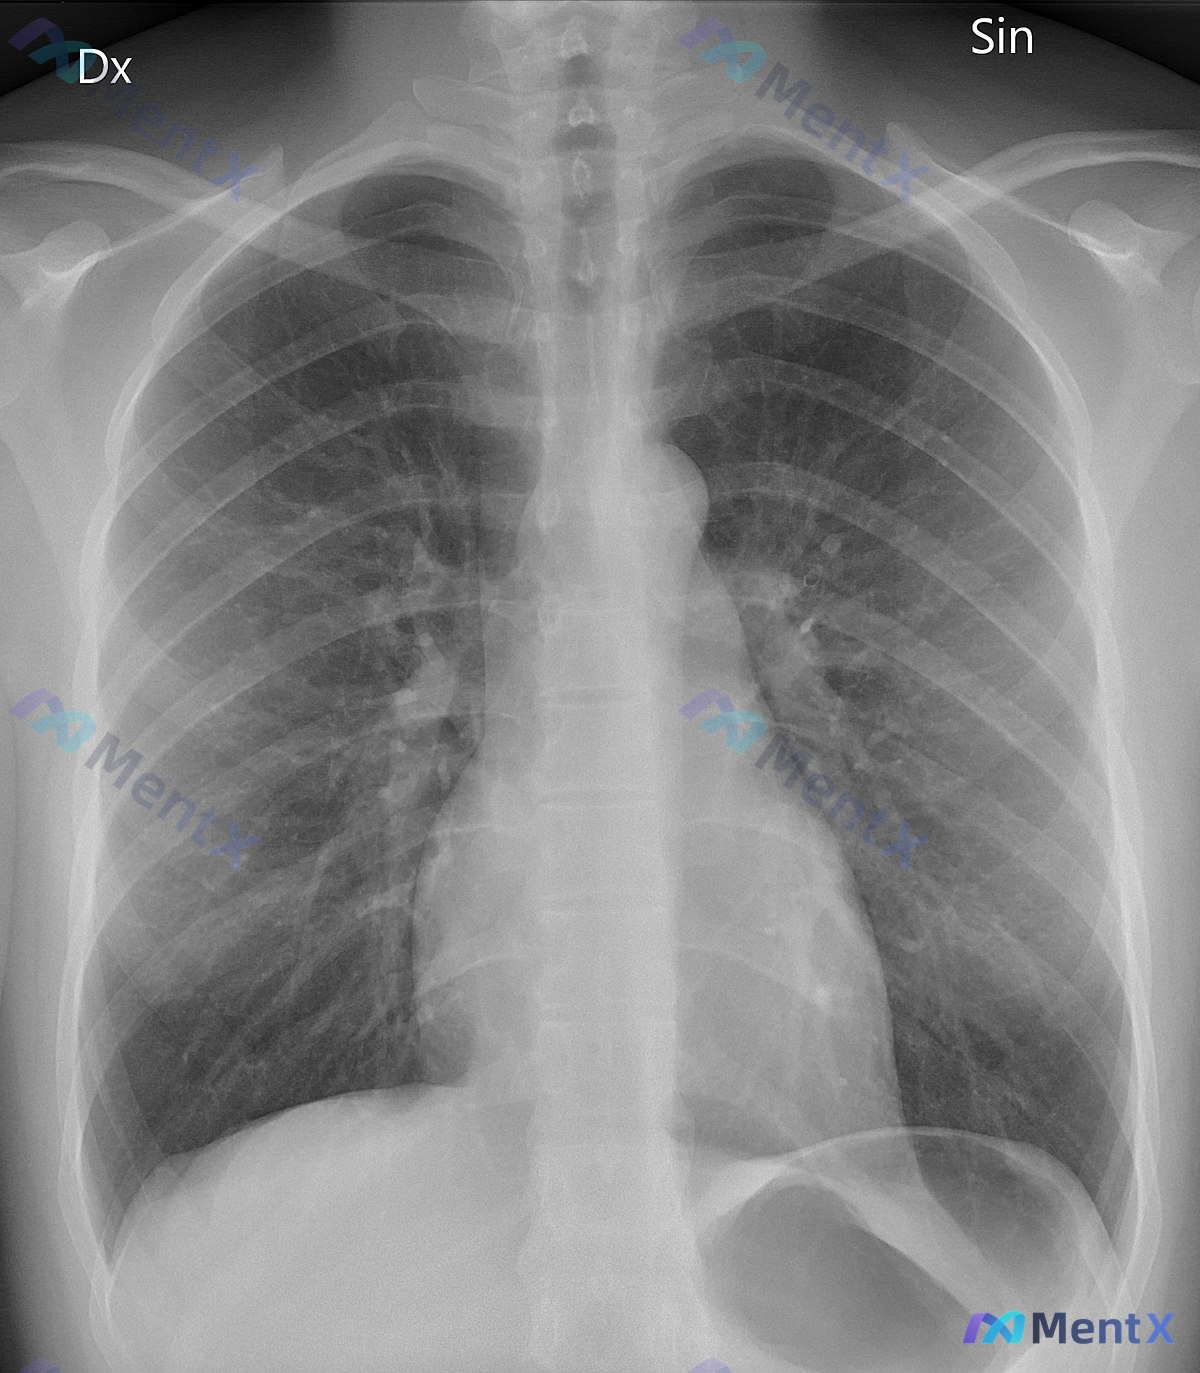

- 胸片(正位):未见明显实质性肺部病变、无胸腔积液等